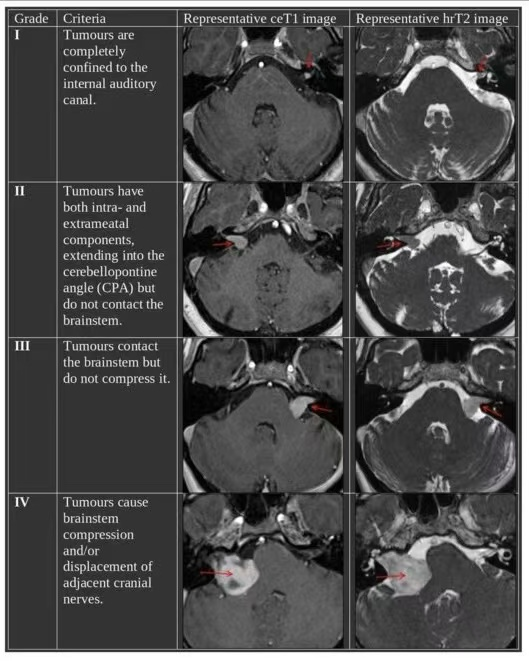

Koos分级

Koos分级系统将听神经瘤分为1至4级,其中4级表示肿瘤体积较大,通常已达到脑干受压状态。

Koos 4级听神经瘤手术难度大、风险高,需要经验丰富的神经外科团队进行精细化操作,才能有效减少术中并发症和术后功能损伤。

听神经瘤Koos分级